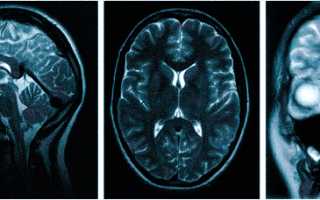

Множественные ишемические очаги при сосудистой деменции на МРТ: отсутствие памяти на недавние события и неадекватное поведение не являются признаками старости, своевременная диагностика деменции и патогенетическая терапия помогут замедлить прогрессирование болезни

МРТ — обследование, которое проводят не только при головной боли. Магнитно-резонансная томография поможет установить причины следующих жалоб:

Врач определяет не только вид обследования, но и его объем. Иногда требуется дать оценку не только структурам мозга, но и воротниковой зоны: голова может кружиться и болеть при шейном остеохондрозе, грыже, воспалении нерва и пр.

МРТ головного мозга — необходимость при некоторой эндокринологической патологии, так как гормональные нарушения могут быть обусловлены сдавлением опухолью важных структур, отвечающих за деятельность желез. Томограммы показывают изменения со стороны гипоталамуса и гипофиза. МРТ при головных болях и головокружении, при подозрении на опухоль или сосудистые патологии можно пройти в диагностическом центре “Медицина Северной столицы”.